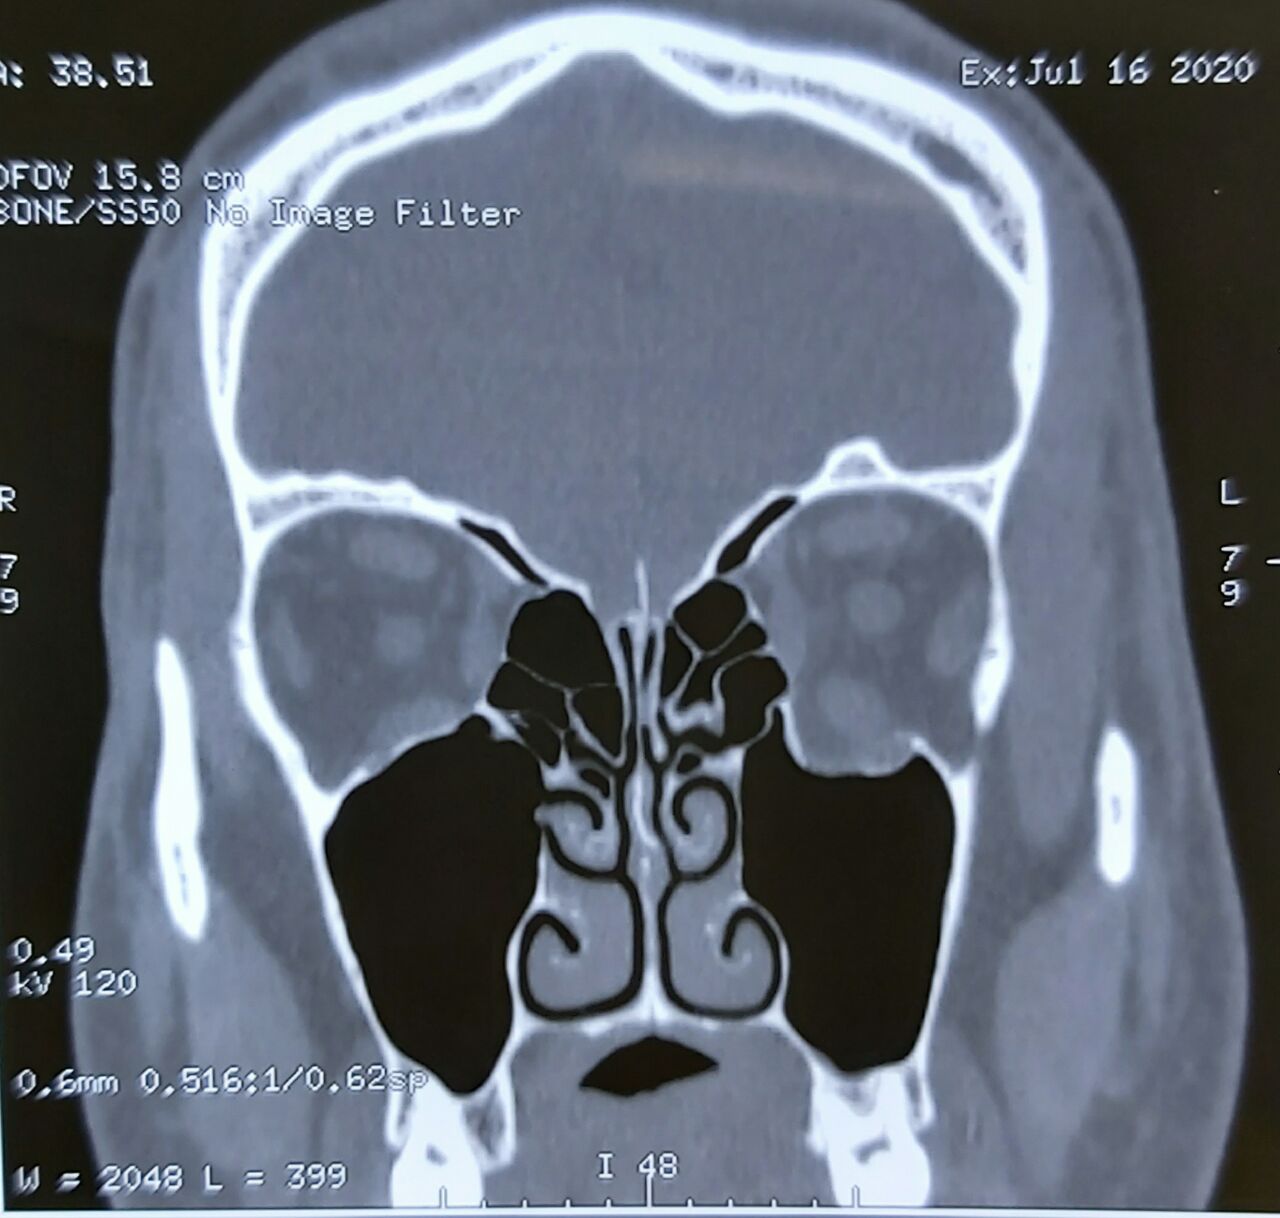

وقال أختصاصي جراحة الوجه والفكين بالمستشفى، والطبيب المعالج الدكتور رضوان الطائي، في حديث صحفي، أن فريق طبي برئاستنا نجح بعملية تثبيت كسر محجر العين بإستخدام الصفائح المعدنية.

مبيناً، أن المريض يبلغ من العمر (32) عام أصيب بكسور معقدة في عظام محجر العين نتيجة تعرضه إلى حادث.